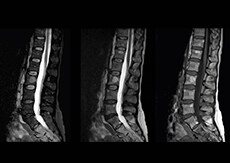

“In our lumbar spine MRI, the value of mDIXON TSE is so obvious. Normally we perform T1 and T2 scans in sagittal and transverse orientation.It used to take too much time to add a sagittal T2 with good fat suppression.But now, using mDIXON TSE, we get the sagittal T2 fat suppressed images ‘for free’, that is: without adding time.” “Diagnostically that is a great benefit. I sometimes see abnormalities in the fat suppressed sagittal T2 that would be quite challenging to notice in the T2 without fat suppression. There have been several diagnoses that I could make easier because of our exam setup with mDIXON TSE, such as sacrum insufficiency fractures and sacroileitis; these were more challenging with our previous exam setup.”